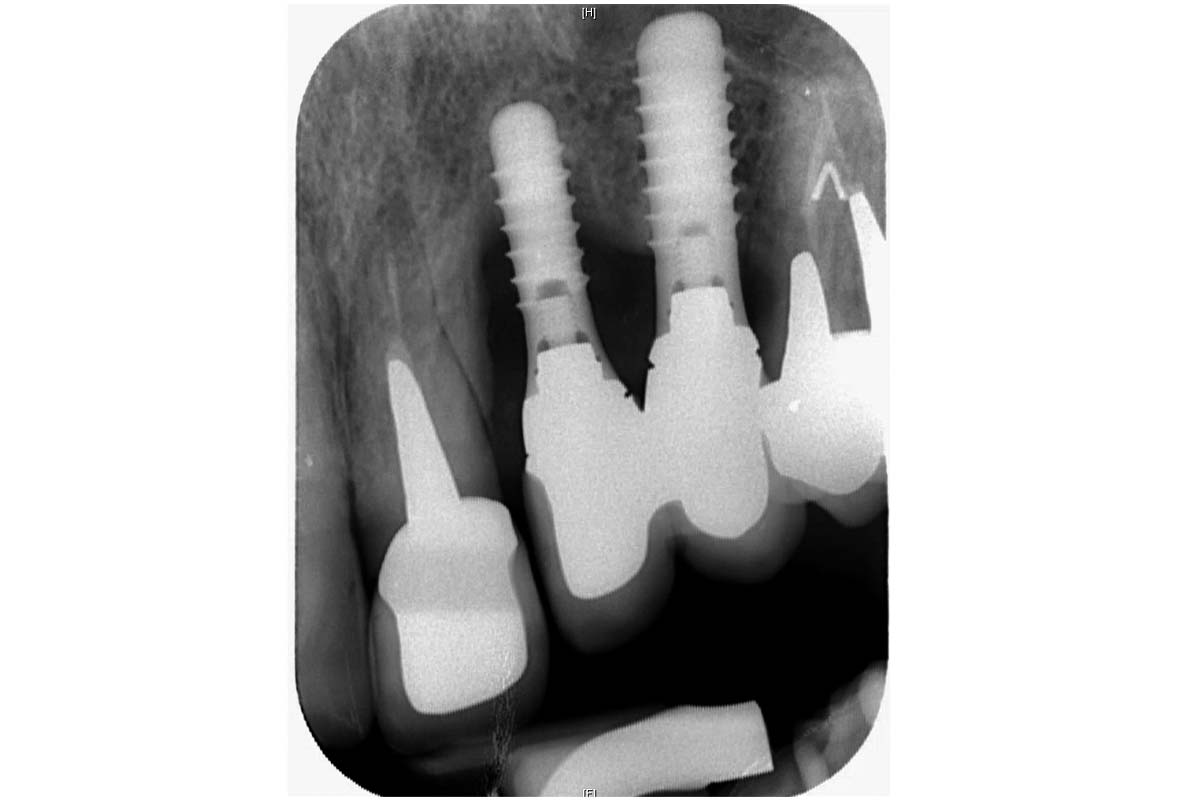

Initial x-ray showing bone loss around implants placed 5 years ago in another dental clinic